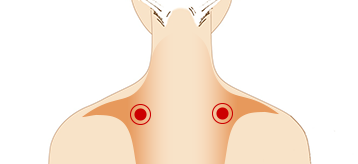

어깨가 뻐근할 때 승모근 지압

-

오랜 시간 앉아있거나 스트레스를 받으면 쉽게 뭉치는

승모근을 양손으로 꽉 잡은 상태에서 목을 좌우로 돌린 후 놓아줍니다. 어깨의 뻐근함과 피로감을 풀어줍니다.

위치 : 고개를 숙였을 때 가장 볼록 튀어나오는 뼈에서

양쪽 어깨 끝까지 이어져 있는 근육